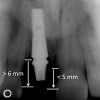

Figure 7  These images summarize the various dimensional assessments that underscore the Rules of Six guidelines, which enable simple planning for uncomplicated single-tooth dental implant therapy: Finding mesiodistal or inter-radicular (Fig 7), buccolingual (Fig 8), and inter-occlusal (Fig 9) distances of 6 mm can assure uncomplicated implant placement and restoration.

Figure 7

Figure 8  These images summarize the various dimensional assessments that underscore the Rules of Six guidelines, which enable simple planning for uncomplicated single-tooth dental implant therapy: Finding mesiodistal or inter-radicular (Fig 7), buccolingual (Fig 8), and inter-occlusal (Fig 9) distances of 6 mm can assure uncomplicated implant placement and restoration.

Figure 8

Figure 9: These images summarize the various dimensional assessments that underscore the Rules of Six guidelines, which enable simple planning for uncomplicated single-tooth dental implant therapy: Finding mesiodistal or inter-radicular (Fig 7), buccolingual (Fig 8), and inter-occlusal (Fig 9) distances of 6 mm can assure uncomplicated implant placement and restoration.

Figure 9

The typical minimal mesiodistal dimension that may be considered for simple single-tooth replacement of an anterior tooth is 6 mm. This may not seem to be an impediment to implant placement; however, several common anatomic situations are often encountered. While the typical dimension of a lateral incisor is greater than 6 mm in the mesiodistal dimension, teeth are often lost without immediate placement, and the bound edentulous space may be reduced. Natural tooth crowding with rotation may result in less than 6 mm of mesiodistal dimension. Another concern is proximal root convergence leading to less than 6 mm of space for implant placement despite the dimension available for the crown. Finally, lateral incisor agenesis that is treated by orthodontics may not always provide 6 mm of space for implant placement or may result in proximal root convergence. There must exist 6 mm of mesiodistal bone dimension between adjacent teeth to permit an implant (> 3.5 mm in diameter) to be placed with greater than 1 mm of bone at mesial and distal interproximal locations (Figure 2 and Figure 3). The advent of narrow implants (eg, 3 mm) provides a new opportunity to address smaller (approximately 5 mm) mesiodistal dimensions.